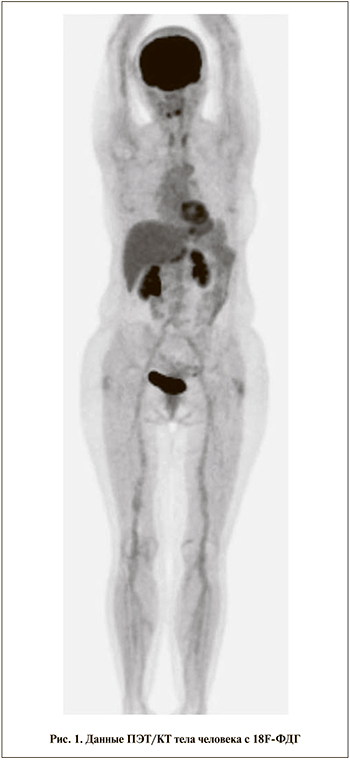

Результаты. Проводимая в рамках настоящего исследования стандартная процедура ПЭТ/КТ с 18F-ФДГ на первом этапе заключалась в сканировании всего тела человека независимо от анатомической зоны интереса (рис. 1).